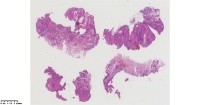

角化棘皮瘤?

性别

男

年龄

45岁

临床诊断

一般病史

面部包块

标本名称

图2

倾向脂溢性角化病。